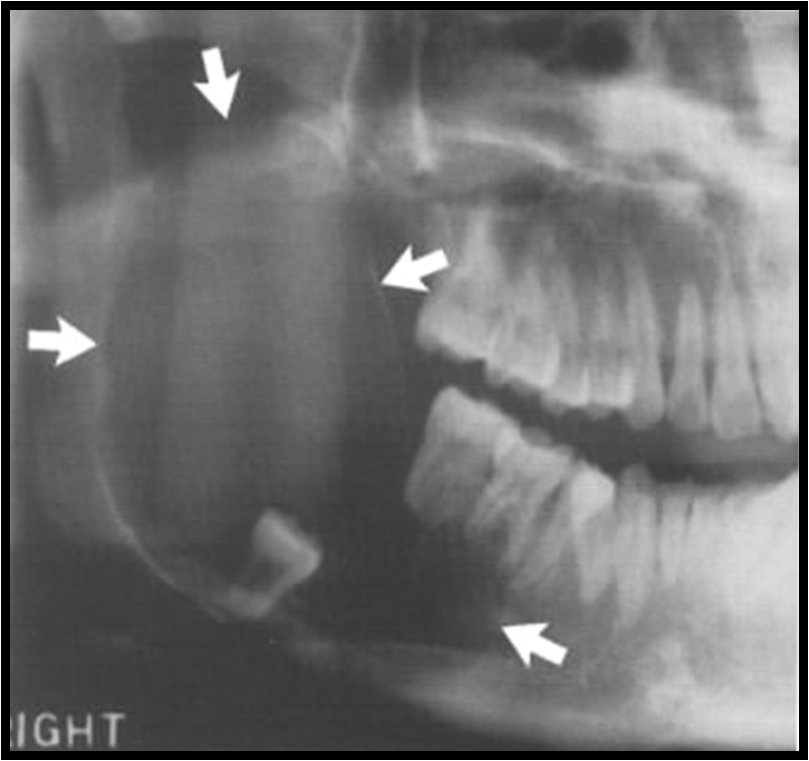

RADIOGRAPHIC FEATURES

Location.

The mandibular first molar

It is always located in the buccal furcation of the affected molar .

Periphery and shape

circular shape with a well-defined cortical border

Superimposed over the image of the roots of the molar.

Internal structure

The internal structure is radiolucent.

Effects on surrounding structures.

Tipping of the involved molar so that the root tips are pushed into the lingual cortical plate of the mandible , and the occlusal surface is tipped toward the buccal aspect of the mandible

If the cyst is large enough, it may displace and resorb the adjacent teeth and cause a considerable amount of smooth expansion of the buccal cortical plate.